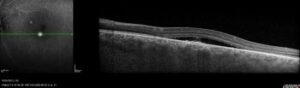

- Le diagnostic se fait à l’aide de photographies du fond d’œil, de clichés en autofluorescence et d’un OCT.

- Bilan : Le diagnostic se fait au fond d’œil et à l’OCT, et doit être confirmé par une OCT-angiographie ou une angiographie à la fluorésceine et parfois une angiographie au vert d’indocyanine lors du bilan initial.

- Un OCT s’il y a un œdème maculaire.

- Macula bombée est une anomalie décrite récemment par le Professeur A. Gaudric. Il s’agit d’un épaississement en dôme de la sclére au niveau de la macula. Elle peut entrainer une baisse de vision. Le diagnostic se fait à l’OCT. Un décollement séreux rétinien peut se voir au sommet du dôme. Il n’y a pas de traitement.

- Le fovéoschisis est un clivage entre les différentes couches de la rétine au niveau de la macula. Il évolue de façon très lente et n’entraine pas forcement de baisse de vision. Le diagnostic se fait à l’OCT. La surveillance est de rigueur. Si le fovéoschisis entraine une baisse de vision notable, une chirurgie pourra être envisagée à type de vitrectomie+/-pelage+/-gaz.

Une surveillance ophtalmologique régulière, au moins annuelle, est donc nécessaire en cas de myopie forte. Le bilan ophtalmologique doit comporter un examen clinique standard avec l’acuité visuelle corrigée de loin et de prés, la prise du tonus intra-oculaire, l’examen des segments antérieurs à la lampe à fente (analyse du cristallin notamment) et un fond d’œil dilaté. De plus un OCT maculaire permettra dans de nombreux cas un diagnostic plus précis.

Il se fait au fond d’œil, il est confirmé à l’OCT et à l’angiographie. L’angiographie à la fluorescéine permet d’éliminer une autre maladie et de repérer le point de fuite ; dans certains cas l’angiographie au vert d’indocyanine est indispensable pour guider le traitement ou éliminer un néovaisseau choroïdien.